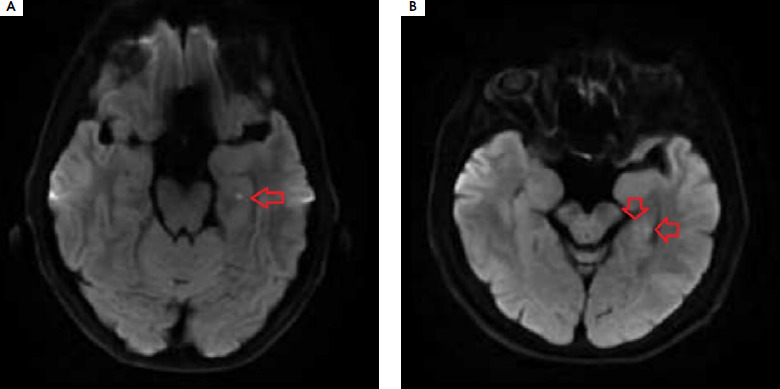

Purpose: Transient global amnesia (TGA) manifests as acute short-term memory disturbances lasting up to 24 hours. The pathophysiology of the disease remains unclear. This paper presents the case of a patient with recurrent TGA, in whom a shortening of coagulation times and high blood pressure peaks were observed during each acute phase of the disease, suggesting transient increased blood coagulability and transient dysregulation of autonomic blood pressure control.

Case description: A 59-year-old patient with medical history of migraine and arterial hypertension was diagnosed with recurrent TGA (two episodes within a year). Each time, upon admission to hospital, high blood pressure peaks were recorded and activated partial thromboplastin time (aPTT) and prothrombin time (PT) were shortened with gradual normalization over the following days.

Comment: The shortening of aPTT and PT may suggest a relationship between TGA and transient blood coagulation disorders in the acute phase.